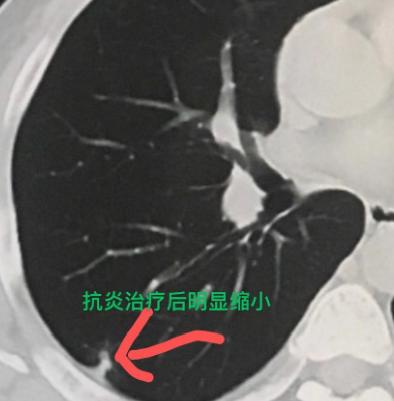

他的肺结节是怎么缩小的?这位30多岁的男性患者,一个多月前因为一直咳嗽、咳痰,吃了药也不见好,就去医院做了检查。当地医生建议他做个CT,结果发现右肺长了个结节。 这个结节一看确实让人紧张——个头不小,而且是个完全实性的。当时医生告诉他,有可能是肿瘤,小伙一听心情沉重,立刻开始多方求医,最后找到我咨询。 仔细看了CT片,我发现这个结节密度比较均匀,虽然实性,但里面藏着一个很小的小空洞,而且空洞壁很光滑。 根据我的经验,这更像是炎症引起的,就建议他先尝试抗炎治疗两周看看。 结果很让人欣慰:一个月后复查CT,那个结节明显缩小了,只剩下一点痕迹。这也证实了它确实不是肿瘤,而是一场“虚惊”——只是炎症感染引起的结节。这样一来,也避免了一次不必要的手术。 其实在临床上,我们常常会通过短期的观察或者药物试验,来帮助判断肺结节的性质。 很多朋友一查出肺结节,就特别着急,经常问我:“医生,这个结节能消掉吗?”“有没有什么药可以吃?”“听说某某药有效,我能用吗?” 我想和大家说明的是:如果结节是由急性炎症引起的,那么在炎症期及时进行抗感染治疗,结节是有可能缩小甚至消失的; 但如果结节是肿瘤性的,那一般靠药物是消不掉的。所以发现肺结节先别慌,找专业医生评估,很多时候只是有惊无险。[作揖][玫瑰]